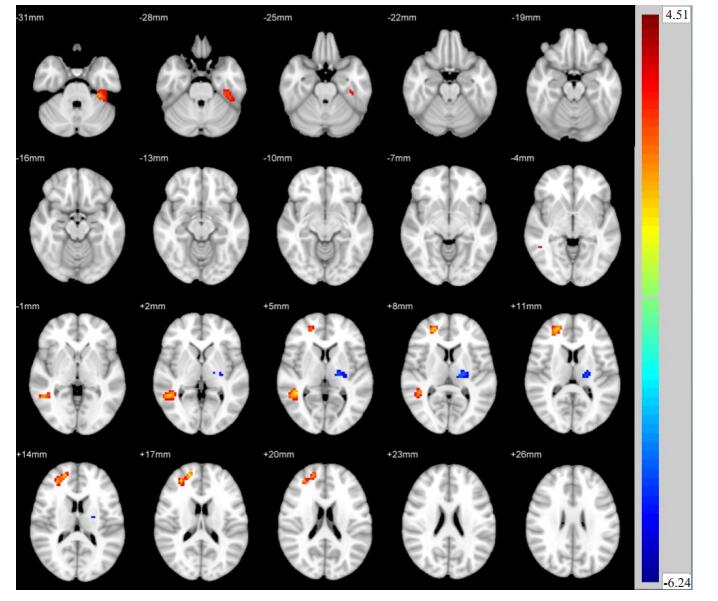

两独立样本t检验显示,与Non- DPN组相比,Painful DPN组左侧颞下回、右侧中央后回ReHo值升高,而后扣带回、右侧顶下回、左侧顶上回ReHo值降低(P < 0.05,图 1,表 2)。与Non- DPN组相比,Painless DPN组左侧颞下回、右侧颞中回、右侧额上回ReHo值升高,而左侧丘脑ReHo值降低(P < 0.05,图 2,表 3)。Painful DPN组与Painless DPN组间ReHo值无显著统计学差异(P>0.05)。

图 2 Painless DPN组与Non-DPN组比较ReHo差异区域 Fig.2 Regional differences in ReHo between painless DPN group and non-DPN group. |

| 表 3 Painless DPN组与Non-DPN组比较ReHo差异脑区 Tab.3 Brain regions with abnormal ReHo in painless DPN group and non-DPN group |

我们发现,Painless DPN组较Non-DPN组左侧丘脑局部一致性减低。丘脑是除嗅觉外所有感觉传至大脑皮层的集中部位,是皮质下感觉的最后中继站,起到重要的感觉加工和信号调制功能[21]。有研究表明[22],维持丘脑神经元功能可能是糖尿病患者感知神经性疼痛症状的先决条件。本研究中,Painless DPN组丘脑局部神经元活动降低,提示丘脑神经功能受损,这也许可以解释为何部分DPN患者不出现神经性疼痛症状。

Painful DPN组及Painless DPN组在左侧颞下回均显示出较Non-DPN组增高的局部一致性。左侧颞下回在语义认知功能中起重要作用[23]。这种静息状态下特定脑区神经元活动增强的机制可能是DPN患者出现的一种额外的功能活动代偿,以弥补其他脑区神经元活动的下降。既往研究[24-25]表明,大脑结构和功能可通过重组和代偿的机制来代替受损的神经功能。临床上,DPN患者目前能维持相对正常的认知功能或许是这种代偿的结果。然而,复杂的神经功能和各个脑区的交互作用均参与了脑功能活动[26],因此,这种代偿机制仍需更深入的研究。